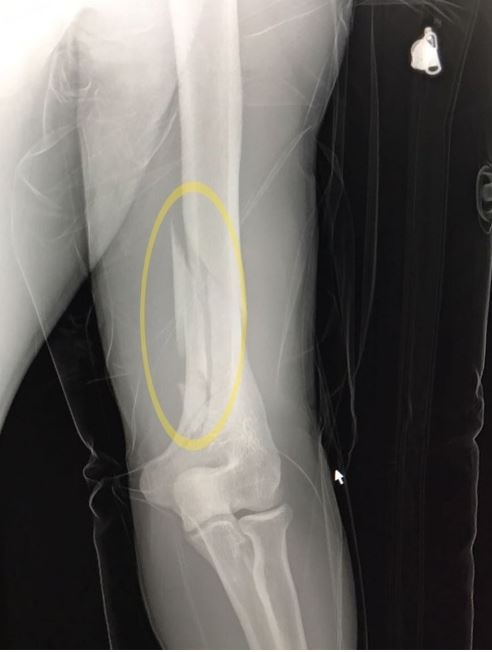

"Ameliyat için 8 saat aç olması lazım. Maça başlarken Fernandao su içmiş. Koluna blok yaptık. Gece kolunu uyuşturduk. Çok parçalı bir kırıktı."

"Ameliyat zor oluyor. İnşallah kaynayacak ve eski sağlığına kavuşacak. Ameliyata 3 arkadaş girdik. Bacaklar sağlam olduğu için bazı sporları yapabilir ama minimum 3 ay sürer. Vidalarla kaynaştırdık. Vidalar vücutta kalıyor. Dışarıdan rahatsızlık yaratmadığı sürece uyumlu metaller kalabilir."

Konya maçında ciddi bir sakatlık geçiren Fernandao, Çağatay Öztürk tarafından ameliyat edildi. Kulüp doktoru Burak Kunduracıoğlu, dirsek ile omuz arasında 5 parçalı bir kırık meydana geldiğini belirterek, "Sahalara dönüş süreci tahmin ediyoruk ki 2-3 ay sürecektir" dedi.